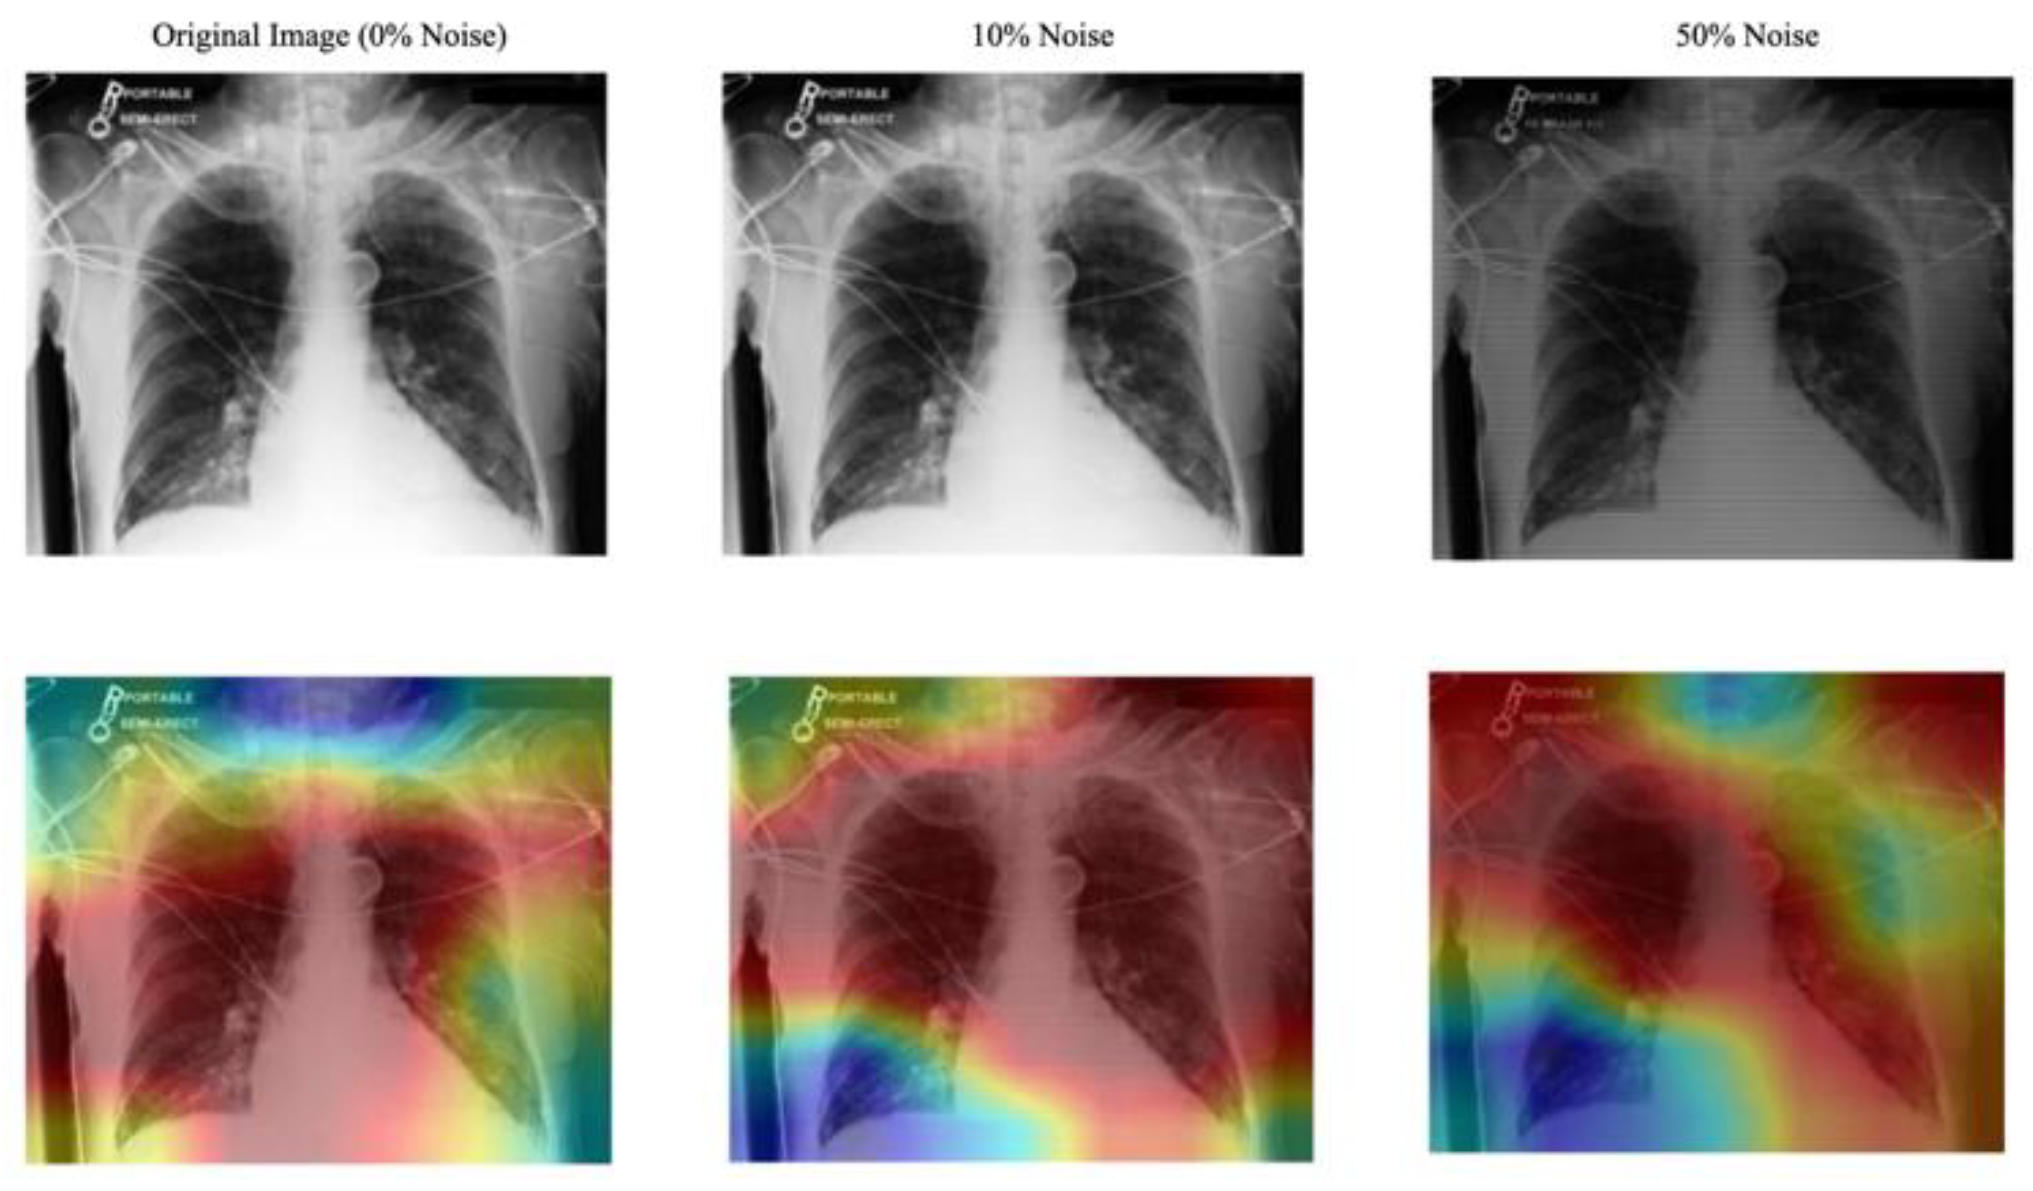

- Evaluation of the Approach. We evaluate our approach to maintain robust performance under noisy conditions, which shows resilience to misaligned fixation maps. We further assess the interpretability of the model utilizing Grad-CAM, ensuring that the generated visual explanations correspond to the expert-annotated RoI. This alignment enhances the clinical reliability of the model's predictions.

C. Explanation

C. Evaluation